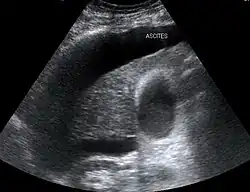

The use of ultrasound has become the standard of care when preparing a patient for paracentesis. Confirmation of an ascitic effusion reduces the risks associated with a dry or blind tap of the abdomen. Anatomic landmarks, such as the midline linea alba approach, were traditionally used as reference points for needle insertion. Phased array or curvilinear ultrasound transducers are typically used in the hospital and outpatient setting to identify ascites in the abdominal cavity. Fluid within the abdominal cavity appears hypoechoic or anechoic (black) on ultrasound. Morison's pouch (hepatorenal recess) is a common starting location in concordance with ultrasound FAST (focused assessment with sonography for trauma) exam. Fluid collection can occur in a number of different locations and may be difficult to find, especially if the patient only exhibits a small volume of ascites. Measurement of the amount of fluid within the abdominal cavity is not necessary or very successful. Identification of sufficient fluid within the abdominal cavity for fluid analysis or to achieve a therapeutic benefit is all that is required to proceed to paracentesis. Ultrasound guidance of the paracentesis can also be used as an additional safety measure to ensure the needle stays within the ascitic fluid and avoidance of important vessels within the abdominal cavity.[5]